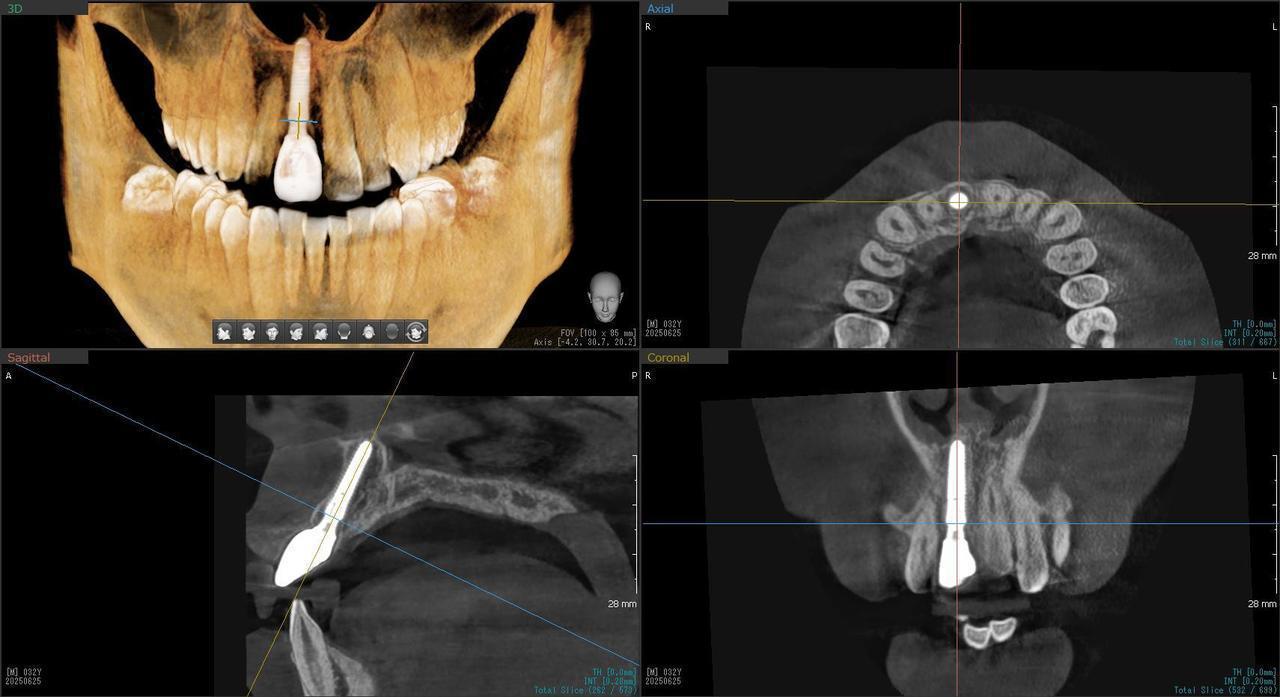

Before

枚方市のインプラントの症例

After

H・M様 女性 60代

症状としては、左上6番の歯根が歯根が破折したために、炎症が起き、上顎洞底までの及ぶ大きな骨欠損がおきていた、

治療法としては、動揺がひどくなってきて、炎症の症状もあったため、抜歯を希望。抜歯後にインプラント治療を希望したために、CTを撮影したところ、かなりの骨欠損が生じていた。インプラントは不可能か大幅な増骨手術が必要なるようなケースであったが、ご自分の骨が少し残っていた部分にエクストラワイドインプラントで固定をとることと、グラフトレスサイナスリフトを併用する計画を立て、インプラント埋入術を施行。2か月後、インプラントがデータ測定上安定したために、光学印象で印象を行い、2か月半後に上部としてジルコニアクラウンを装着して治療を終えています。

治療結果として、大幅な骨欠損があったが、2か月半という短時間で治療を終えることができた。通常のサイナスリフト等の大幅な増骨手術を行った場合、患者様に、肉体的、金銭的、時間的な負担をかけることになったが、グラフトレスサイナスリフトとエクストラワイドインプラントを使用することにより、そのことを避けることができた。

治療の期間・回数:治療回数インプラント埋入後6回

治療の価格:363000円(税込)

治療費の内訳:インプラント基本料(フィックスチャー(メガジェンインプラントANYONE) 及び手術費用、投薬費用、レントゲン費用、インプラント上部費用(アバットメントおよびジルコニアクラウンの費用用)330000円(税込み)左上6グラフトレスサイナスリフト費用 33000円(税込)

治療のリスクや副作用:手術後に、痛みや腫れ、出血、合併症などを引き起こす可能性があります。噛む感覚がご自身の歯と異なる場合があります。見た目がご自身の歯と異なる場合があります。手術後にメインテナンスを継続しないと、インプラントが抜け落ちる可能性があります。